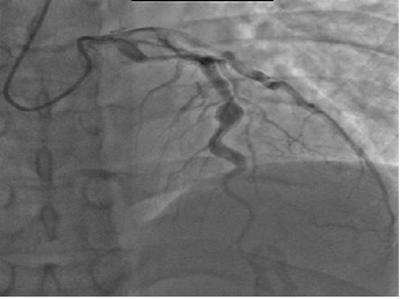

Quindi, non essendo disponibili test di laboratorio specifici, la SK viene diagnosticata in base ai criteri clinici e, se presenti, all'osservazione degli aneurismi coronarici mediante ecocardiografia, angiografia coronarica o TC delle coronarie. Nel momento in cui si sopsetti una SK, le eventuali complicanze cardiache devono essere attentamente indagate, ma è ovvio che l'esecuzione di un esame diagnostico con l'utilizzo di un mdc in un bambino di 4 anni non sia opportuno. Ed è per questo che ci si avvale di metodiche quali  l'ecocardiografia. Nell'immagine viene mostrata una coronarografia con aneurisma del ramo discendente anteriore dell'arteria coronaria sinistra. In questi casi, bisogna porre il sospetto che l'aneurisma sia un esito di una SK misconosciuta. Per quanto riguarda la TC questa richiede una riduzione della frequenza cardiaca tramite l'utilizzo di un beta-bloccante e ovviamente tale atteggiamento è improponibile per un bambino con un'età massima di 4 anni. Per fortuna oggi è possibile effettuare una diagnosi precoce e applicare di conseguenza il corretto schema terapeutico, per cui le complicanze a livello cardiaco risultano essere molto rare.